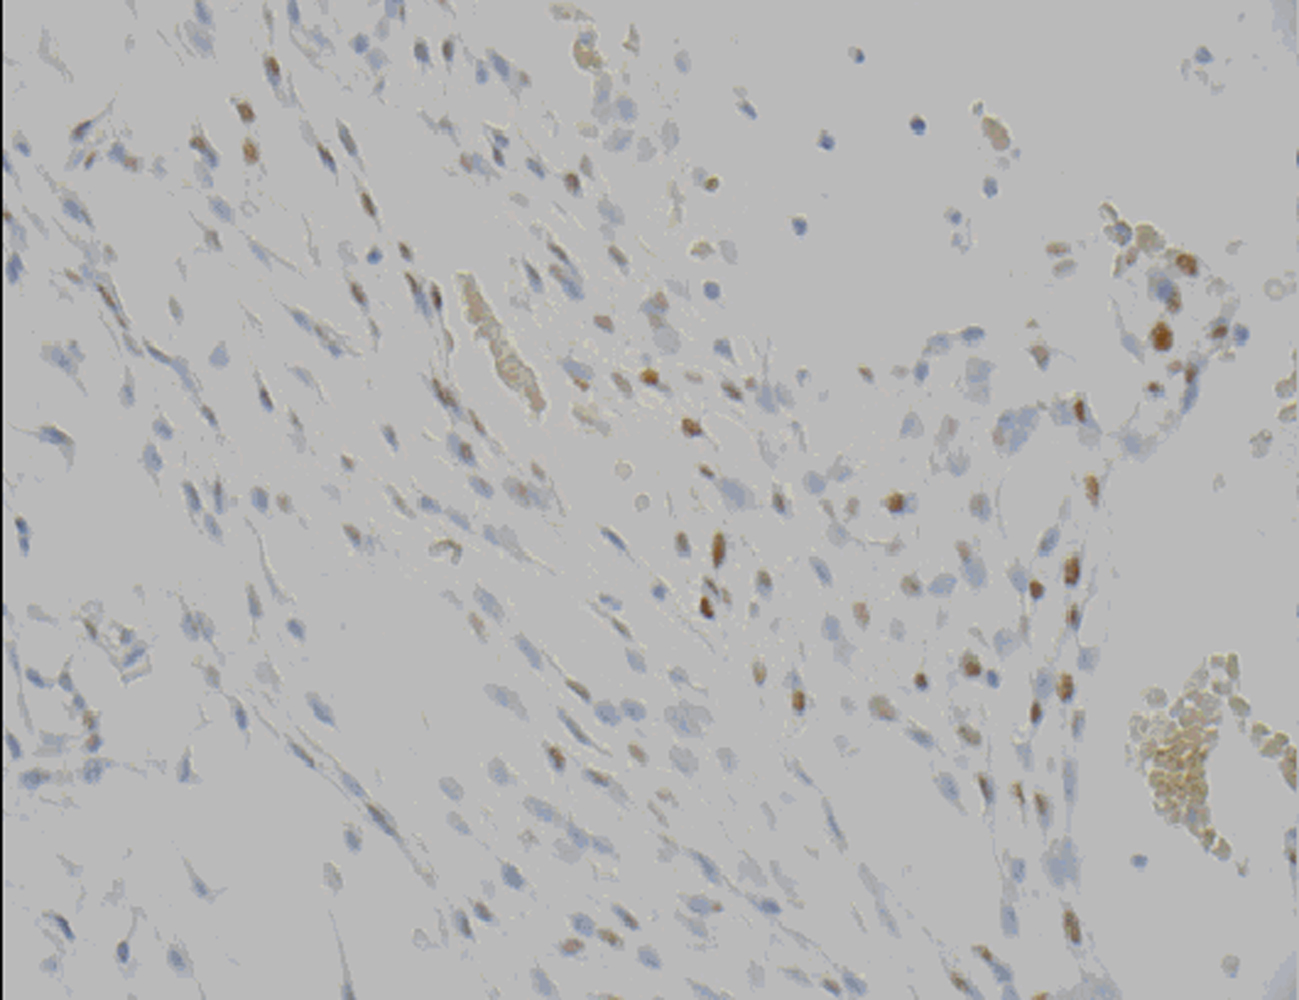

Microscopic examination revealed a tumor admixed with unorganized blood clot/hemorrhage (Fig. 5). The tumor is composed of whorl formation and chordoid growth pattern with eosinophilic tumor cells in a myxoid matrix (Fig. 6). The tumor cells are positive for vimentin, epithelial membrane antigen (EMA), and Progesterone receptor (PR) (Fig. 7) immunostains. The tumor cells are negative for Oestrogen receptor (ER), glial fibrillary acidic protein (GFAP), S-100, and Anti-Cytokeratin(CAM 5.2) immunostains. The histological features and the immunostain profiles are consistent with chordoid meningioma [8, 19].

![]() Click for large image | Figure 7. Progesterone receptor (PR) demonstrates nuclear positivity in chordoid meningioma tumor cells. |